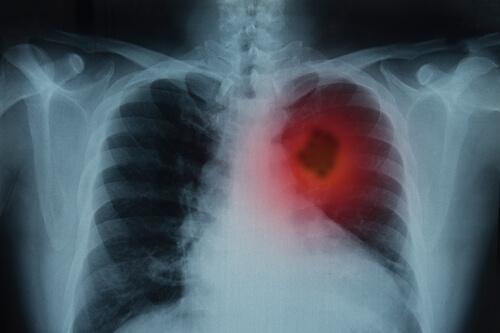

Akciğerleriniz solunum sisteminizin en önemli bölümlerindendir. Burnunuza ve ağzınıza giren hava trake borusundan bronşlarınıza oradan da son olarak ciğerlerinize ulaşana kadar ilerler. Akciğer kanseri belirtileri ölümcül olabilir. Bu yüzden erken dönemde fark etmek önemlidir.

Ayrıca, belirtiler 3 haftadan fazla süreyle devam ederse göğüs röntgeni çektirmek için mutlaka doktorunuzu ziyaret etmelisiniz. Röntgen sonuçlarınıza göre doktor tıbbi geçmişinizi detaylı bir şekilde öğrenmek ve diğer laboratuvar testleriyle birlikte fiziksel bir muayene yapmak isteyebilir.

- Görüntüleme: Bu prosedür sayesinde doktor vücudunuzun iç bölgelerinin görüntülerini görebilir.